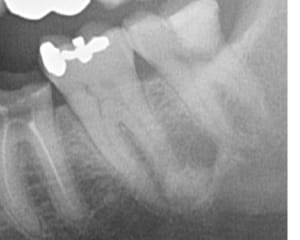

559940449_10163144646462247_7720006236309727129_n.jpg